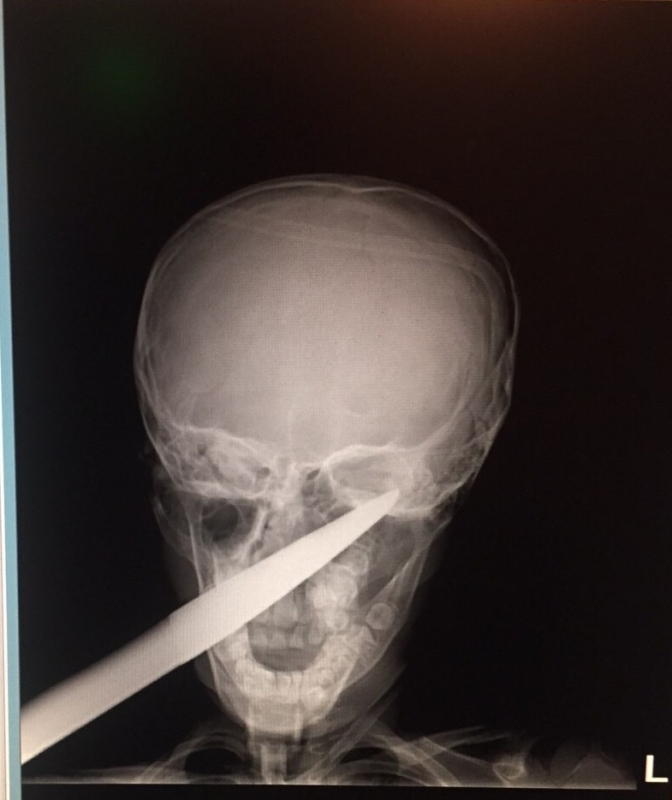

...... Ръждясалото острие минава през цялата буза на детето и опира в черепа зад окото. "Още няколко милиметра и изходът щеше да е фатален", заявиха лекарите.

Гледката наистина е жестока коментираха очевидци след направено рентгеново изследване